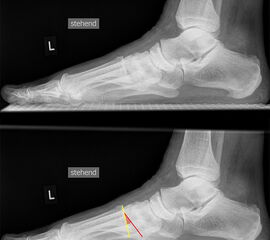

Fuß seitlich mit Belastung

Positionierung:

• Der Patient steht auf beiden Füßen mit gleichmäßiger Lastverteilung.

• Der zur Röntgen der Fuß wird längs des Films positioniert.

• Die Kassette steht senkrecht zum Boden, medial dem Fuß anliegend.

• Der Zentralstrahl wird von lateral nach medial zentriert auf das Kalkaneokuboidalgelenk knapp cranial der Os metatarsale V Basis ausgerichtet.

• Die Röntgenröhre steht 0° horizontal.

Kennzeichen des Röntgenbildes:

• Standardabbildung des Fußes zusammen mit der belasteten d.-p. Aufnahme und der unbelasteten 45° Pronationsaufnahme.

• Überblick über die Fußanatomie und Fußstatik.

• Die seitliche Aufnahme liefert Informationen zur Stabilität des Längsgewölbe und zu den Achsen von Talus, Kalkaneus und Metatarsale I.

• Die Aufnahme wird eingesetzt zur Darstellung von freien Gelenkkörpern sowie knöchernen Veränderungen am Achillessehnenansatz oder der Plantarfaszie.

Besondere Bemerkungen zum Beispielbild:

• Schwere Hallux valgus Deformität.

• Die Sesambeine sind luxiert, ebenso das Großzehengrundgelenk. Luxation des Metatarsophalangealgelenks II.

• Degenerative Veränderungen der tarsometatarsalen (TMT) Gelenkreihe, betont TMT II und III.

Zur Vollansicht und zum Lesen der Bildbeschreibung bitte die Bilder anklicken.